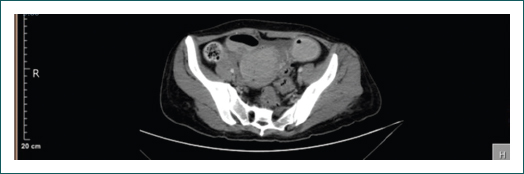

Como parte del protocolo diagnóstico se realiza una tomografía abdominal que reporta probable apendicitis complicada; valorada por el servicio de cirugía general, se descarta la presencia de patología apendicular. Por el antecedente de pérdida de peso cuantificada de 18 kg en 3 meses, ingresa al servicio de medicina interna para inicio de protocolo de estudio, en donde se evidencia en los estudios iniciales anemia normocítica normocrómica, así como trombocitosis. Se realiza radiografía de abdomen simple y en decúbito, que muestra una importante dilatación de asas intestinales a expensas del yeyuno y el íleon. La tomografía de abdomen en fase simple y contrastada muestra una imagen compatible con una zona de estenosis a nivel del íleon distal, a 7 cm de la válvula ileocecal, que de forma secundaria condiciona un proceso pseudooclusivo, además de compresión y desplazamiento de estructuras pélvicas (útero, vejiga y sigmoides) (Figs. 1 y 2).